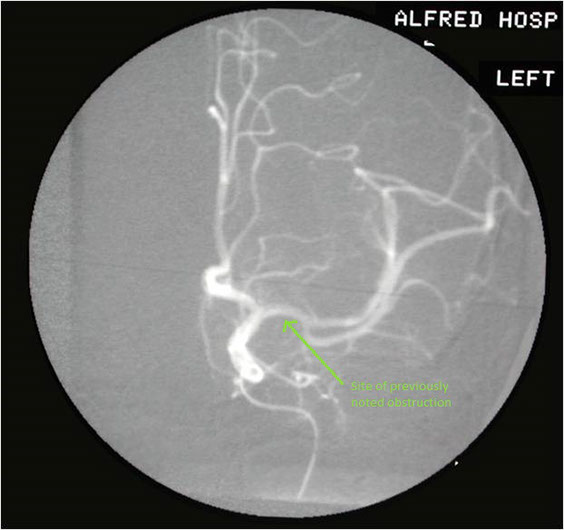

The most favourite subspecialty was angiography and interventional work particularly in the vascular field. This was the first angioplasty performed in the department. This represents atheroma with a focal stricture of the left femoral artery which was dilated with the presented result. Note that the atheromatous process is not limited to one area.

Femoral artery stricture post dilatation. Note the ragged appearance of the dilated atheromatous plaque.

This patient developed several strictures two years apart. This one is a popliteal stricture.

Popliteal stricture post dilatation

And this represents the second stricture two years later in the left lower femoral artery

And this is the post-dilatation image of the femoral stricture.